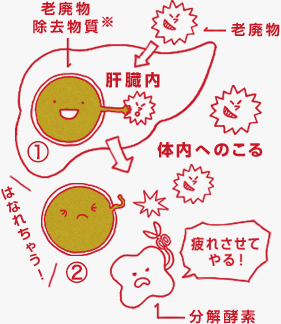

肝臓では、食物から摂取された糖分から作られた「グルクロン酸※」が、疲労の原因となる老廃物などに作用して、それらを処理しています(図①)。不要物は汗や尿に溶けて体外へ排出されますが、水に溶けないものは、そのままでは排出できません。「グルクロン酸※」は、水に溶けない不要物と結合して、水に溶ける状態「グルクロン酸抱合体」に変えています。この抱合体は、分解酵素により、分解されることがあります(図②)。

「グルクロノラクトン」は、この「グルクロン酸抱合体」を分解してしまう酵素の働きを抑えることにより、効率的な排出をサポートするのです。